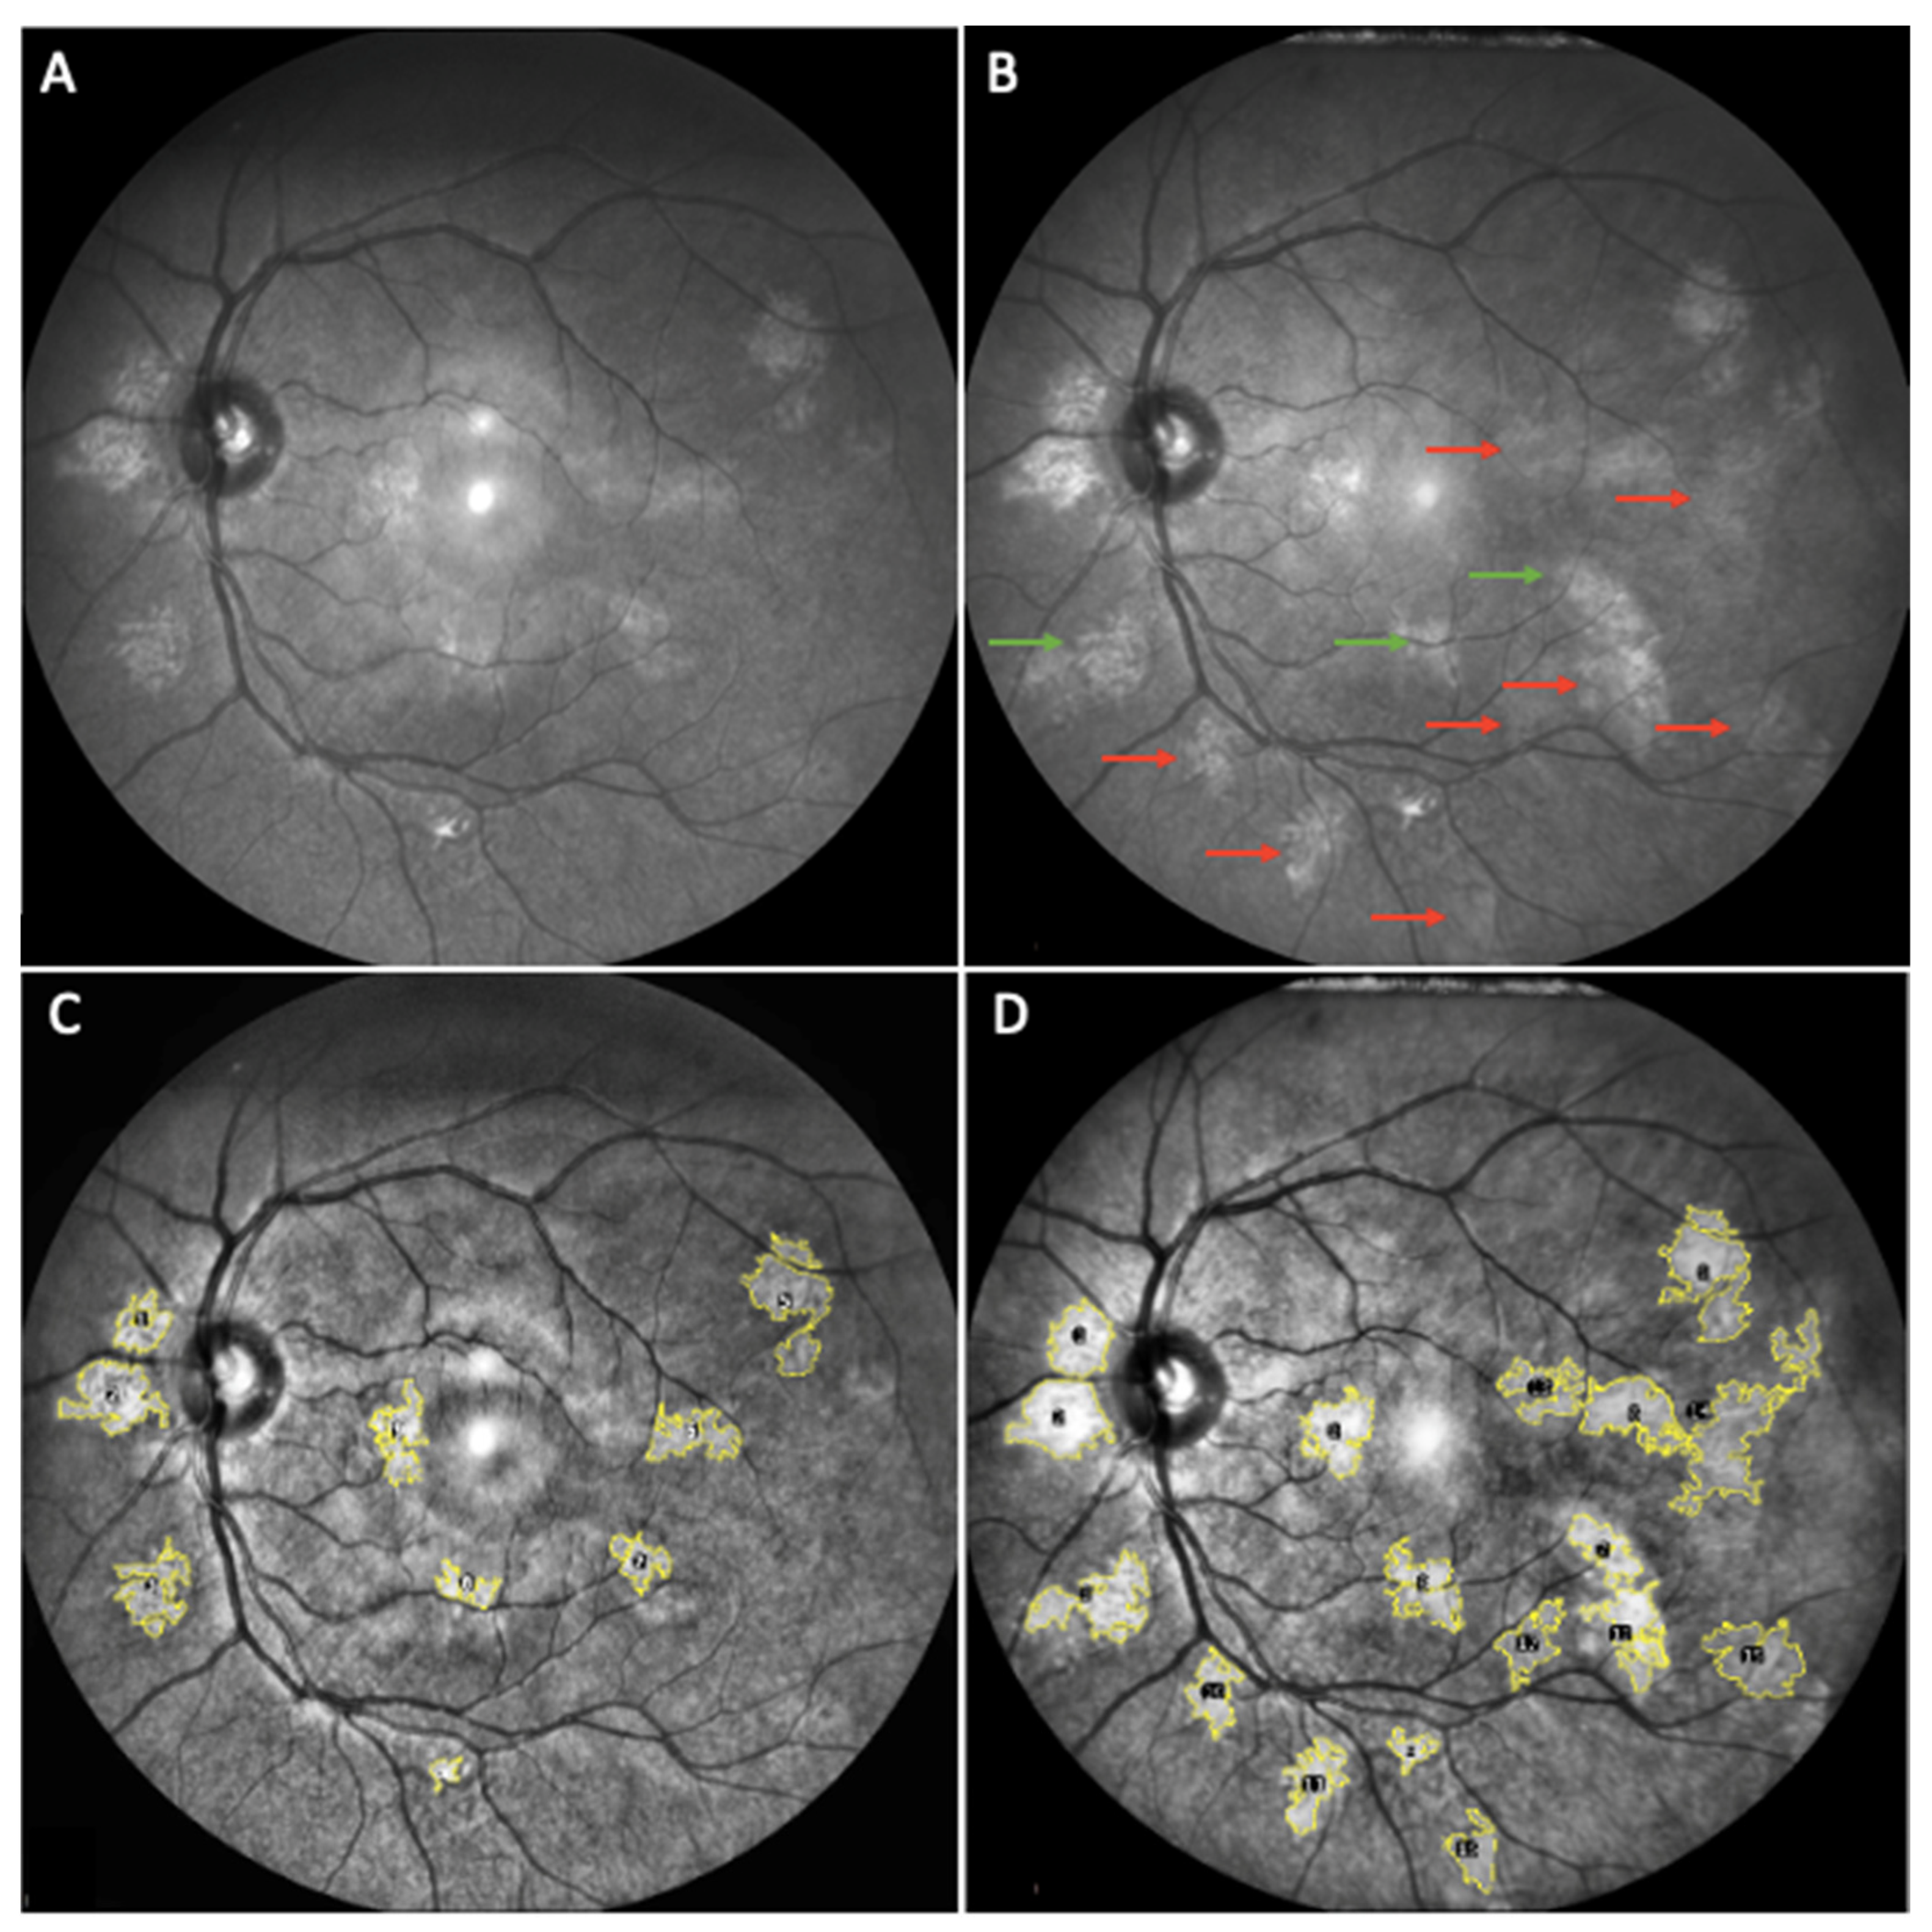

3. Results